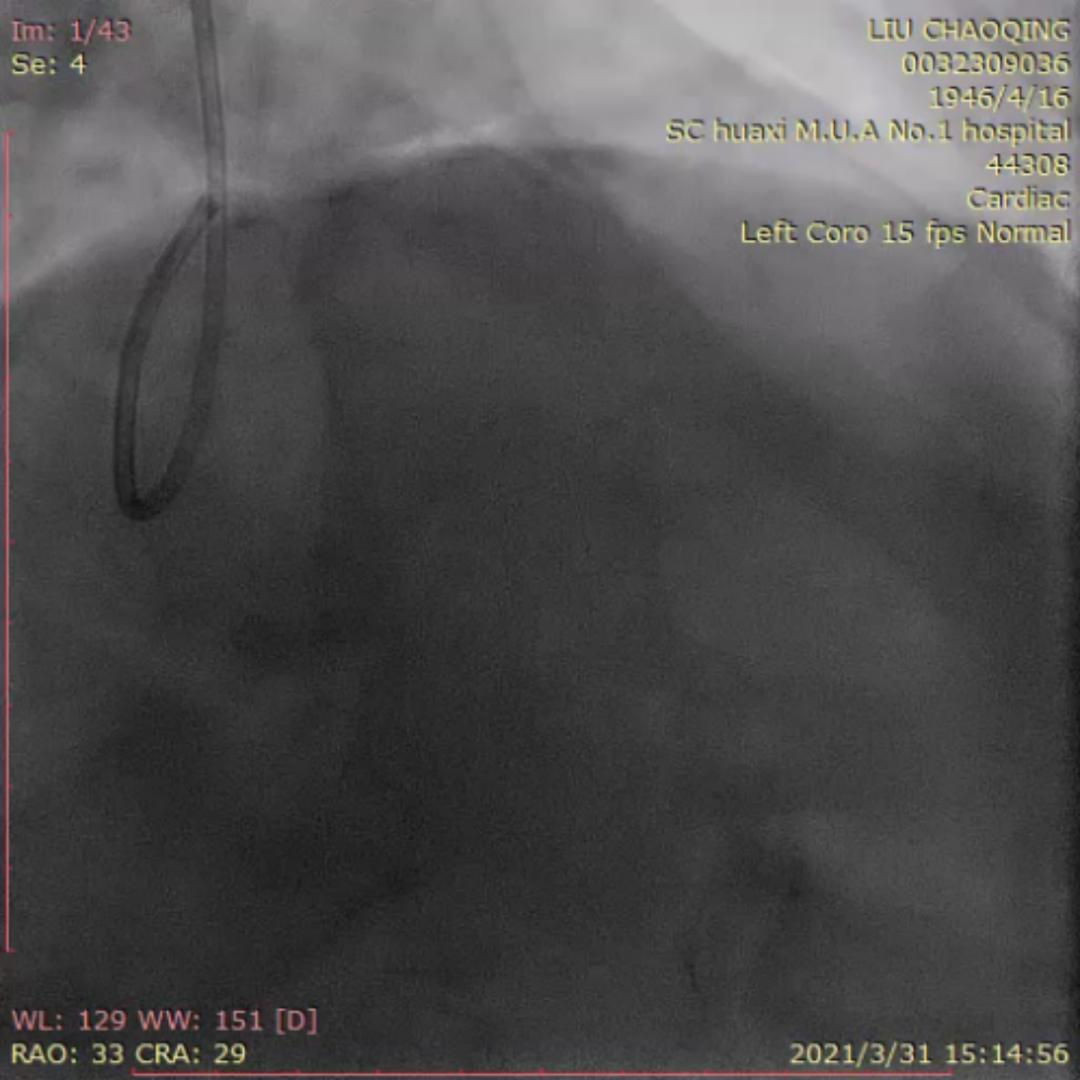

来自四川大学华西医院的李晨教授为大家分享了一例ADR开通前降支CTO的疑难病例。患者为老年男性,反复活动后胸痛6月。当地医院冠脉造影提示前降支完全闭塞,尝试PCI未能成功开通血管。予规范药物治疗,患者仍反复有胸痛入院。患者两段CTO,闭塞段长,钙化重,成角,前次失败,J-CTO 4分,右窦上方侧枝供应间隔-前降支;回旋支自身侧枝供应对角支;右冠无明显侧枝;前降支中段着陆区条件较好,ADR着陆区条件尚可。

患者术中遭遇前降支导丝受阻,对侧和同侧造影前降支远端显影不清的问题。后双侧造影时可见对角支和前降支主支相通。同侧逆向可清晰显示对角支,若进入对角支真腔,可调整方向或通过KDL将导丝放入前降支。随后Pilot 200顺利进入对角支,导丝进入对角支分支。然而随后导丝在第二段闭塞重度钙化处进入假腔,从假腔进入对角支,在远端重回真腔。后启动ADR。最后李晨教授结合病例对逆向及ADR启动时机和ADR穿刺位点选择进行了发表了个人见解。